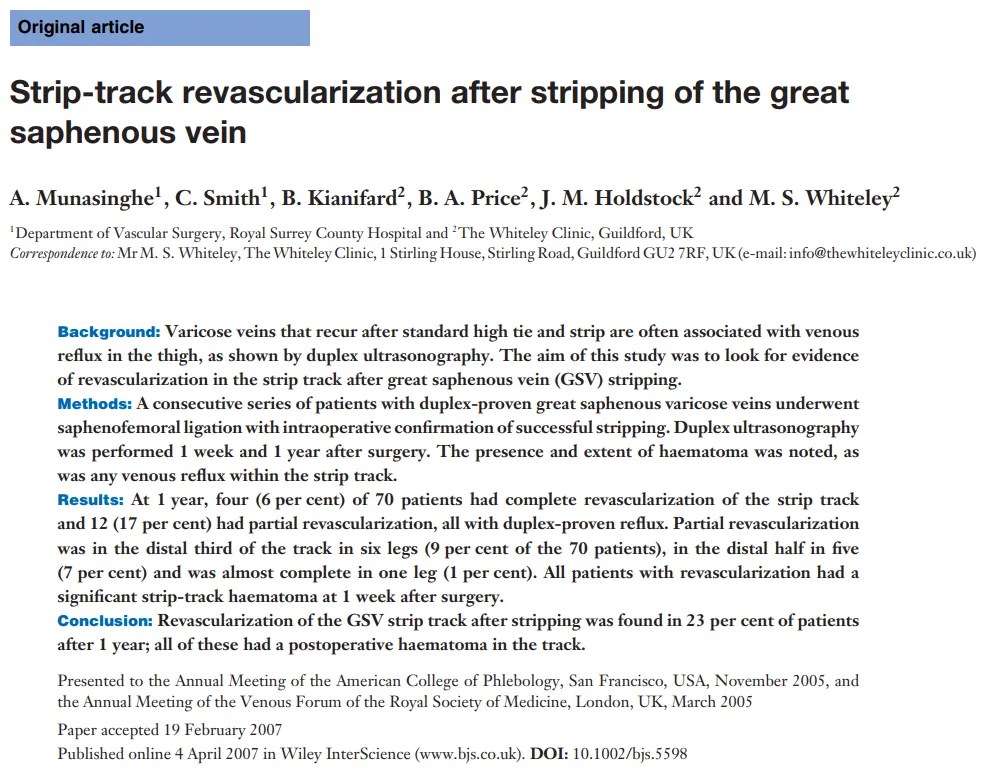

图:(a)静脉超声显示右腹股沟隐筋膜内的原发性瓣膜静脉曲张畸形(PAVA)组织- 大隐静脉 (GSV) 和前副隐静脉 (AASV) 先前消融-箭头显示不同的PAVA血管。(b)同一患者显示PAVA进出一个淋巴结。

图:a 大隐静脉剥脱术后1年大腿剥除处血管再生的纵向超声图像。注意存在多个管道。b 彩色血流多普勒图像显示剥除处血管再生大腿上每个管道都有反流。

图:大隐静脉剥脱术后1年大腿血管再生的横向超声图像,四个管道可见。